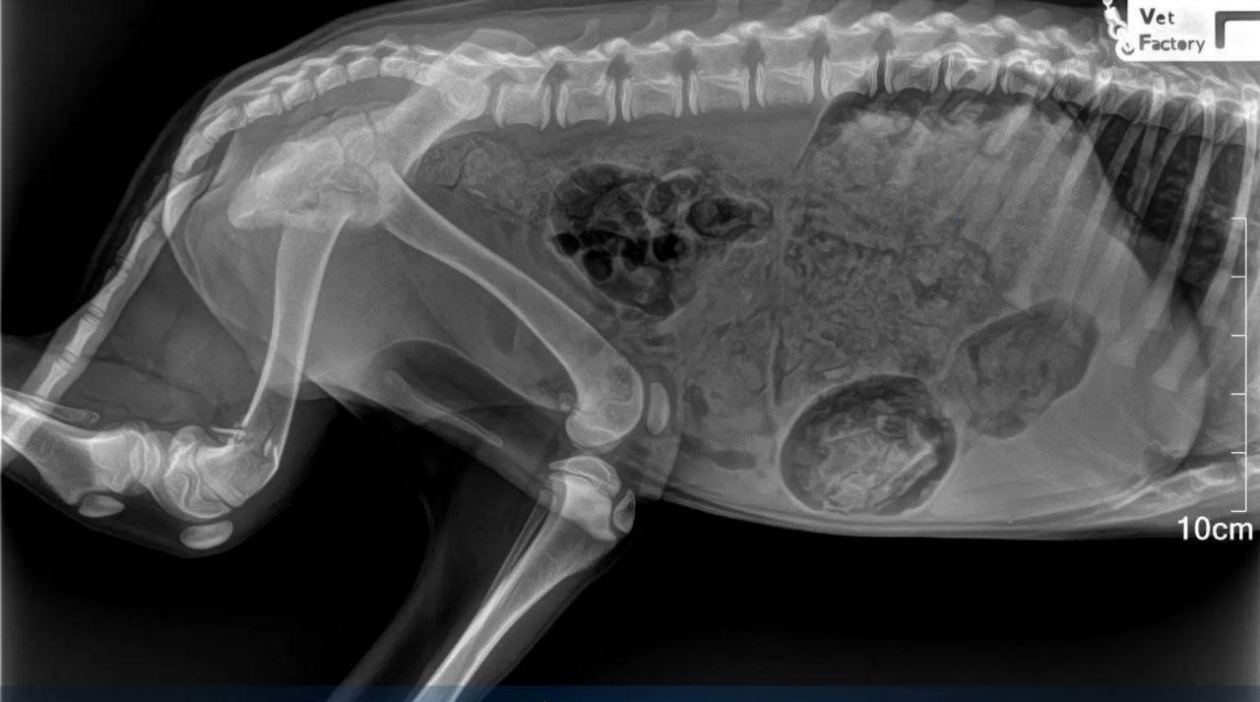

Следствие устанавливает личность человека, выбросившего собаку из окна жилого дома в Лесозаводске. Четвероногая жертва чудом выжила, но получила множественные переломы, сообщила пресс-служба прокуратуры Приморья.

Вопиющий случай жестокости произошел вечером 25 января. Животное сбросили с высоты пятого этажа на улице Пушкинской, после чего собаку обнаружили в крайне тяжелом состоянии. Сейчас правоохранители ищут виновного.